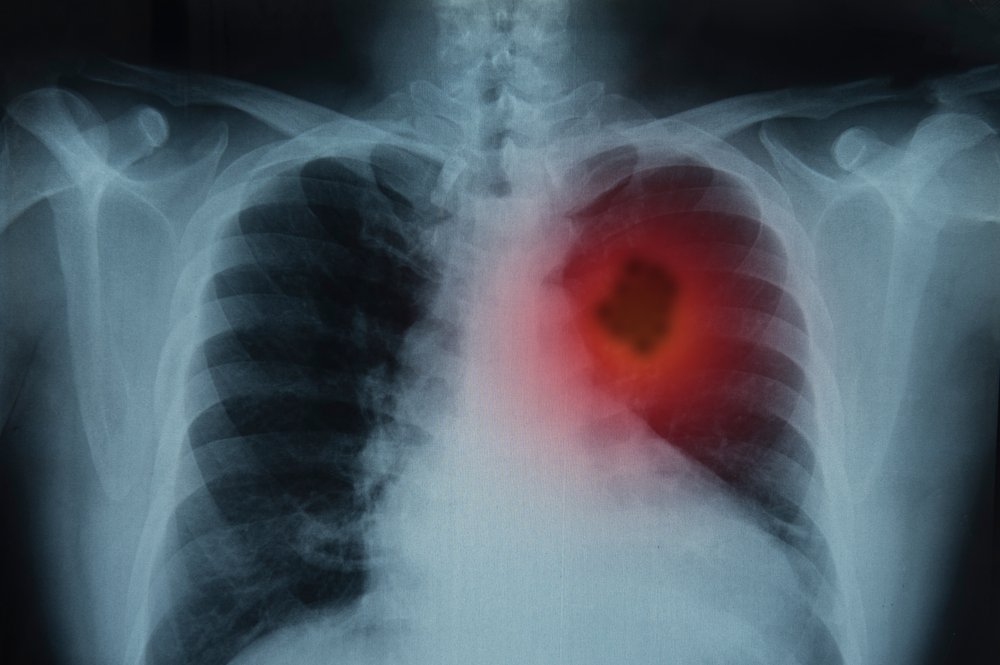

Omul, care primise o pedeapsă de un an de închisoare cu suspendare după ce a fost prins la volan sub influența alcoolului, a cerut instanței să îl scape de una dintre obligațiile impuse. Motivul este unul șocant. A fost diagnosticat cu cancer pulmonar în formă gravă și se află în stare de handicap sever, având nevoie de însoțitor.

Potrivit documentelor medicale depuse la dosar, bărbatul se confruntă cu multiple probleme de sănătate, de la tumori la nivelul plămânilor și bronhiilor până la afecțiuni cardiace și respiratorii care îi fac viața un calvar. Se deplasează cu dificultate, obosește rapid și are nevoie constantă de ajutor chiar și pentru activități simple.